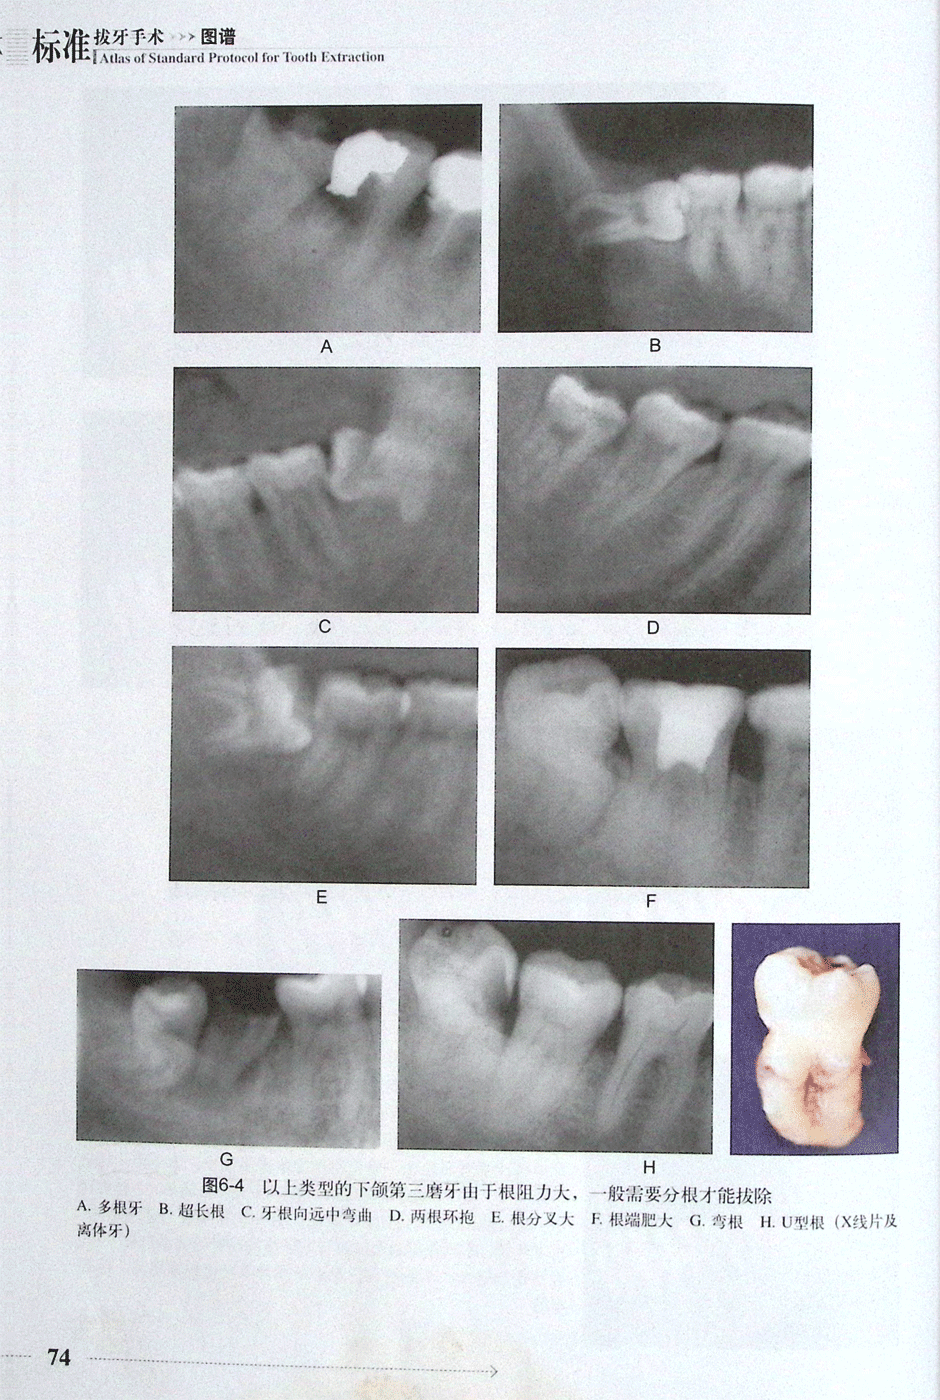

第一节 阻生下颌第三磨牙的拔除(二)